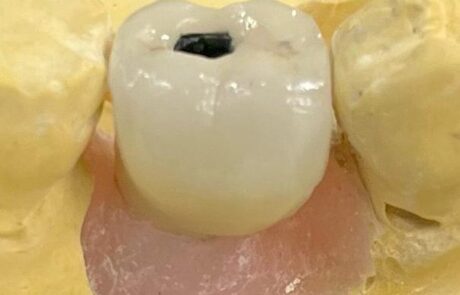

Corona sobre implantes o piezas dentales

Puentes sobre implantes o piezas dentarias